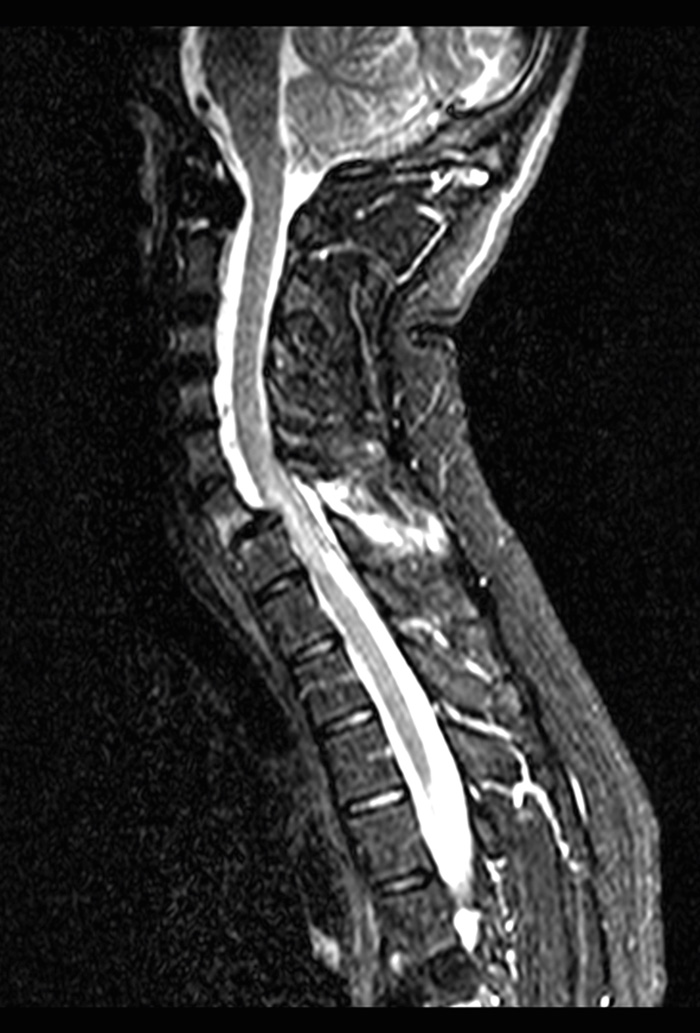

Efterföljande veckor uppvisade patienten progredierande neurologiska symtom i båda armarna som bedömdes vara orsakade av skador på plexus brachialis. Vid en EMG-undersökning kunde man se tecken på såväl nervrot- som plexusskada. Patientens besvär avtog inte. Två månader senare genomfördes en omfattande undersökning med MR, DT och slätröntgen. Då uppdagades en kraftig dislokation C 6–C 7 (Figur 4). När man sedan gjorde en eftergranskning av materialet från den första DT-undersökningen förelåg en synlig subluxation i en (1) facettled C 6–C 7. (LM10647/2004)

Kommentar: Om man tolkat initialbilderna rätt från början borde patienten genomgått MR-undersökning av halsryggen för kartläggning av skadan inför fortsatt omhändertagande. Initial MR-undersökning hade sannolikt avslöjat ligamentskador talande för instabil skada i halsryggen som krävt stabiliserande operation.

Figur 4. MR-undersökning två månader efter skadetillfället påvisade en dislokation med ryggmärgspåverkan på C 6–C 7-nivå.